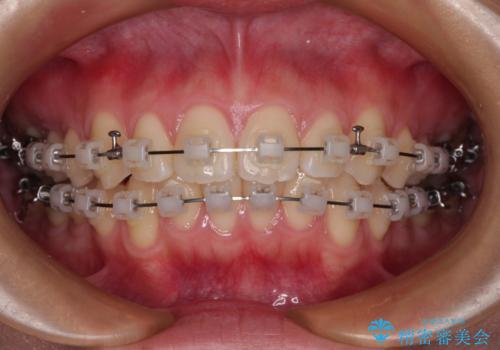

- 矯正装置

- 審美装置

- 治療期間

- 11ヶ月